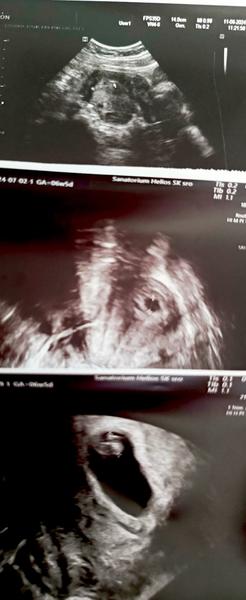

@nikadominikanika ved v niektorych car robia uz na 14dpt sona, aha toto pridavala jedba kocka do skupiny velmi pekne

Ako sa dobre pozerajú tieto obrázky 😍 prajem vám všetko iba to dobre 🍀 nech to ide len dobrým smerom ❤️

@anika02 super 🙂🙂je to na dobrej ceste